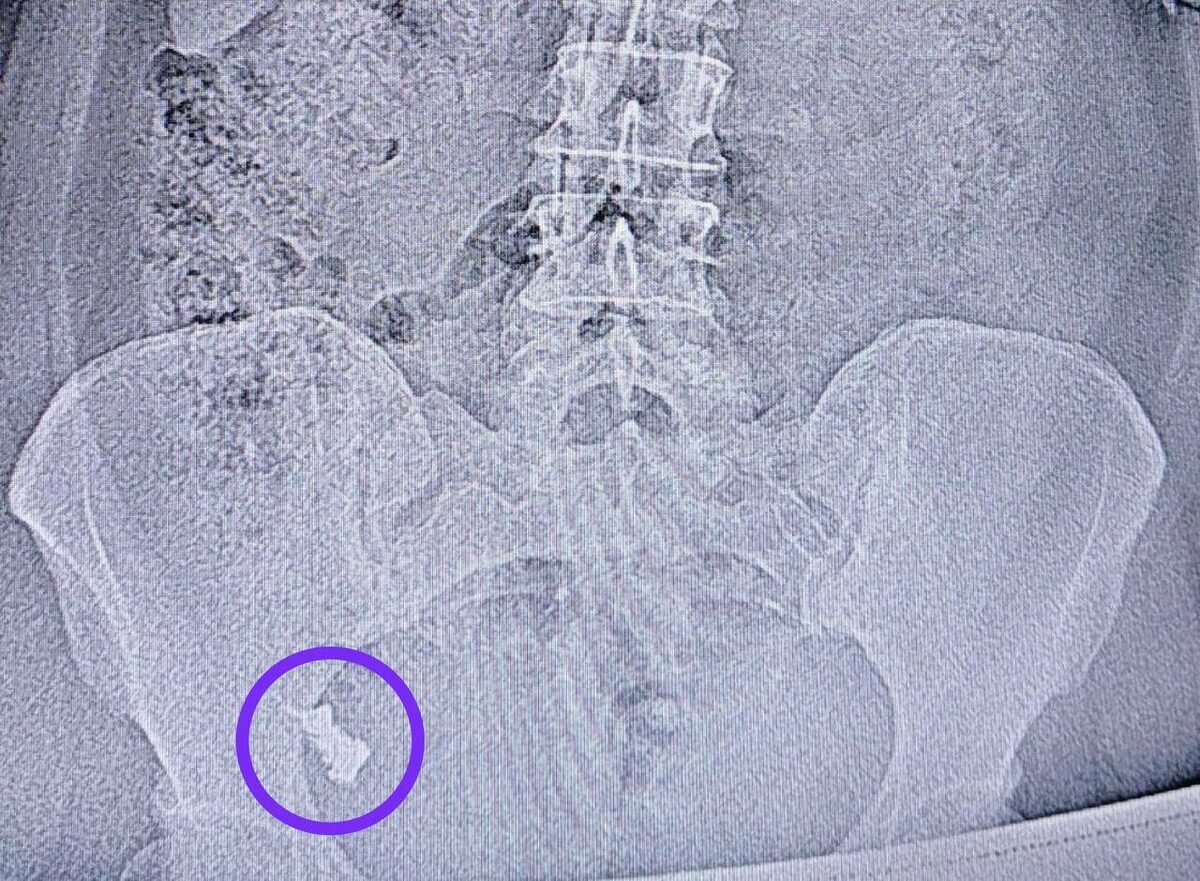

Спустя неделю женщину госпитализировали в хирургическое отделение №1, поскольку протез застрял в области перехода тонкой кишки в толстую.

Врач-эндоскопист Наиль Исхаков во время колоноскопии удалил протез. Процедуру делали под контролем анестезиолога-реаниматолога Елены Чуенковой, поскольку протез находился уже в труднодоступном месте. С анестезией процесс удаления прошел безболезненно.